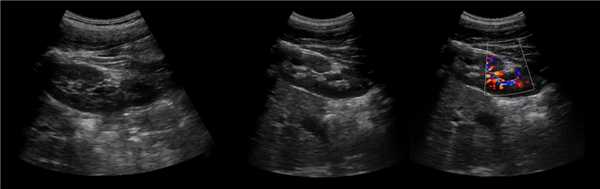

Рисунок. У 37% здоровых новорожденных в первые сутки жизни на УЗИ определяются симптом «белых пирамидок». Преципитация белка Тамма-Хорсфалла и мочевой кислоты вызывает обратимую обструкцию канальцев. К 6 неделям жизни проходит без лечения.

Рисунок. На УЗИ здоровая почка: вдоль основания пирамид (кортикомедуллярный переход) определяются линейные гиперэхогенные структуры с гипоэхогенной дорожкой в центре. Это дугообразные артерии, которые ошибочно расценивать как нефрокальциноз или камни.

Видео. Дугообразные артерии почки на УЗИ

Рисунок. На УЗИ нижний полюс почки отделяет гиперэхогенная фиброзная перемычка; лоханка нижнего сегмента 7 мм. Это вариант нормального строения почки. Почка может быть деформирована, поэтому ее размер и длина немного меньше противоположной. Небольшое расширение лоханки под перемычкой сохраняется пожизненно.

Видео. На УЗИ фиброзная перемычка в почке (вариант строения)